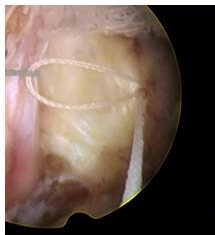

縫合后的纖維環(huán),將外翻的纖維環(huán)向椎間隙人包埋,表面光滑平整,椎間盤內(nèi)部不再與椎管相通,椎間盤內(nèi)的髓核炎性介質(zhì)不易外滲,減少了對神經(jīng)根的刺激,術(shù)后疼痛減輕。并且進(jìn)行纖維環(huán)縫合的病例不需要過多切除椎間盤內(nèi)的髓核,對維持椎間盤的功能和脊柱的穩(wěn)定性有一定的作用。

一次性纖維環(huán)縫合器術(shù)式:

椎間盤髓核摘除+纖維環(huán)修復(fù)術(shù)是目前治療椎間盤突出癥最有效、最安全的微創(chuàng)方法之一。不僅在最大程度上保留椎間盤的功能、減少術(shù)后瘢痕的形成、降低髓核炎性介質(zhì)對神經(jīng)根的刺激,還避免了二次手術(shù)帶來的痛苦以及經(jīng)濟(jì)負(fù)擔(dān)。